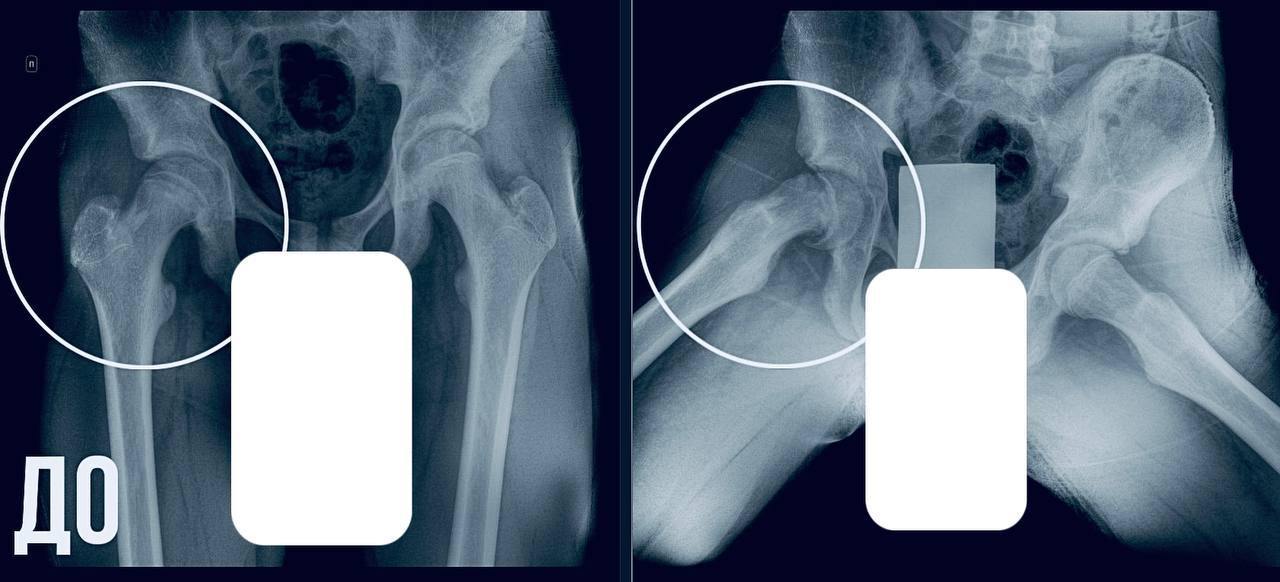

В ходе обследования выяснилось, что у подростка – юношеский эпифизеолиз.

Патология подразумевает смещение головки бедренной кости, характерное для периода активного роста скелета.

— Пациенту требовалась срочная операция. Мы выполнили фиксацию сустава, чтобы остановить смещение и дать ему возможность правильно развиваться. Это убережет юношу от раннего артроза и ограничений подвижности в будущем, — отметил главный врач МОДКТОБ Александр Григорьев.